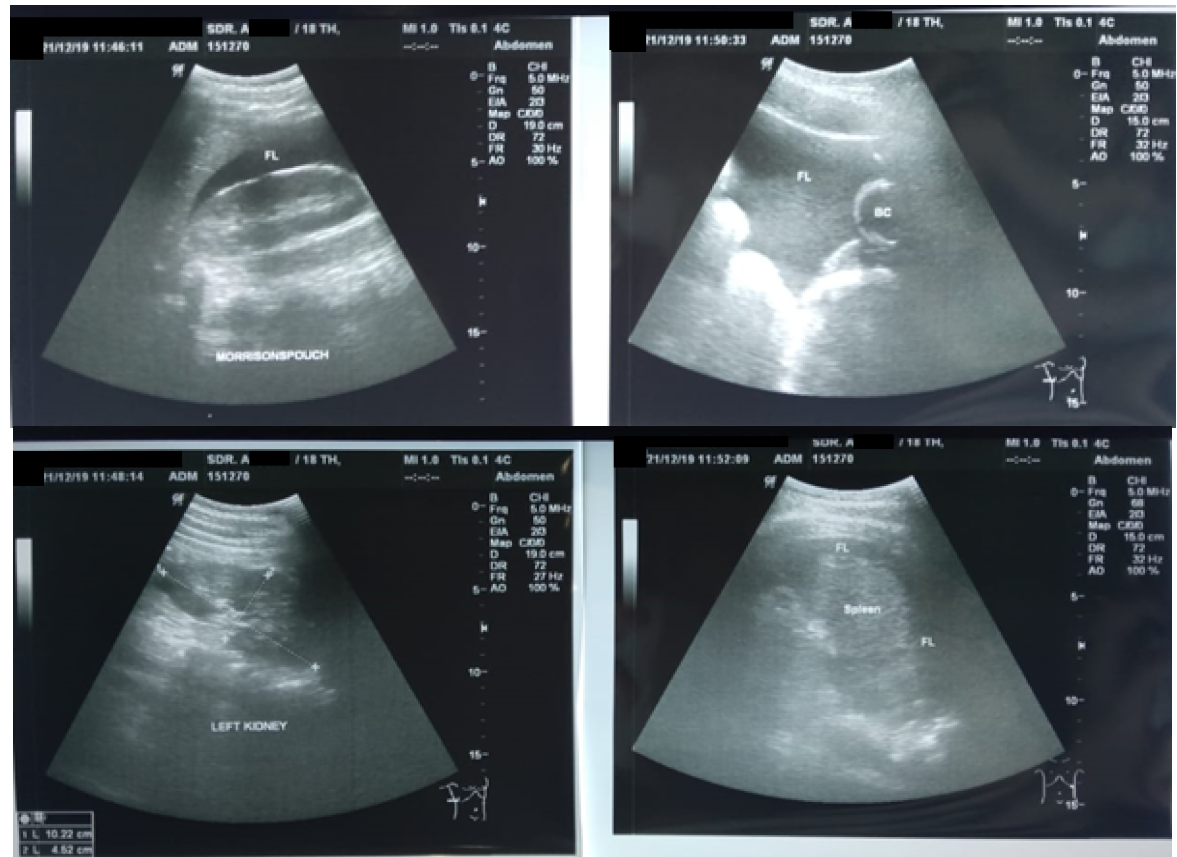

Child C, female, aged 16 years old. Eight hours before admission to the hospital, while the patient was riding a motorcycle wearing a standard helmet, the patient had an accidental fall while avoiding a pothole in the road. The patient fell with her stomach hitting the motorcycle handlebar. After the incident, the patient was conscious, and the patient then complained of pain in the right and left abdominal areas, headache (-), nausea (-), and vomiting (-). The rescuer took the patient to Karanganyar General Hospital. The patient was infused, injected with painkillers, and treated for wounds. The family took the patient to Dr. Moewardi General Hospital Surakarta. The patient arrived at the emergency room two hours after the incident, and abdominal pain was felt in the right and left abdomen. From the primary survey examination, the airway was still free with normal breathing, RR 18 x/m, no circulatory disturbances, BP 90/60 mmHg, HR 84 x/min with GCS E4V5M6, isochor pupil (3mm/3mm), pupillary light reflex (+ /+), lateralization (-/-), and a temperature of 36.5 degrees Celsius. In the secondary survey, the injury was found in the right hypochondria region, with no open wounds, no abdominal distension, bowel movements (+), and pain on palpation in the right upper quadrant of the abdomen. Then, a FAST examination was performed with stable hemodynamics, and FAST (+) was obtained in the Morrison pouch and splenorenal pouch (Figure 5).

Figure 5: FAST Examination (+) on the Morrison Pouch and Splenorenal Pouch

In this case, the patient showed FAST (+) results in the Morison pouch and Splenorenal pouch. The FAST ultrasound results were then followed by a contrast CT scan of the abdomen and obtained liver rupture grade IV, splenic rupture grade II, and free intra-abdominal fluid. In this case, the (+) result in Morison pouch was accompanied by liver rupture grade IV, while the (+) result in Splenorenal was accompanied by splenic rupture grade II.